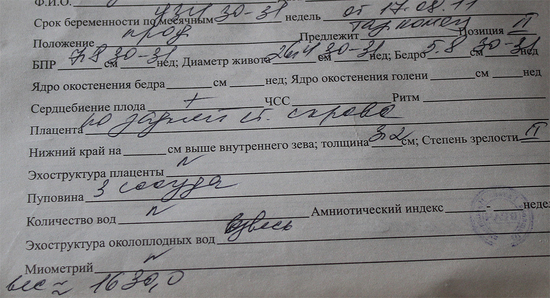

Писать второй раз лень- вот фото заключения:

Писать второй раз лень- вот фото заключения: